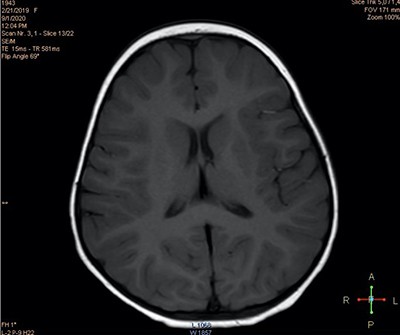

При проведении нейровизуализационного исследования (МРТ 2 Тл) выявлены признаки некоторого усиления МР-сигнала в парагиппокампальной области (см. рис. 2а) и незначительного расширения переднего субарахноидального пространства (см. рис. 2б), что может свидетельствовать в пользу перенесенной гипоксически-ишемической перинатальной энцефалопат На третьи сутки количество эпизодов отведения глаз сократилось до 6, при этом их продолжительность не превышала нескольких секунд.

Рисунок 2а. МРТ-исследование. Признаки усиления МР-сигнала в парагиппокампальной области.

Рисунок 2б. МРТ-исследование. Признаки незначительного расширения переднего субарахноидального пространства.На четвертые сутки количество пароксизмов продолжило уменьшаться и составило всего 2 эпизода длительностью 1–2 секунды. При этом ранее сопутствовавших данным состояниям нарушений координации не отмечалось.